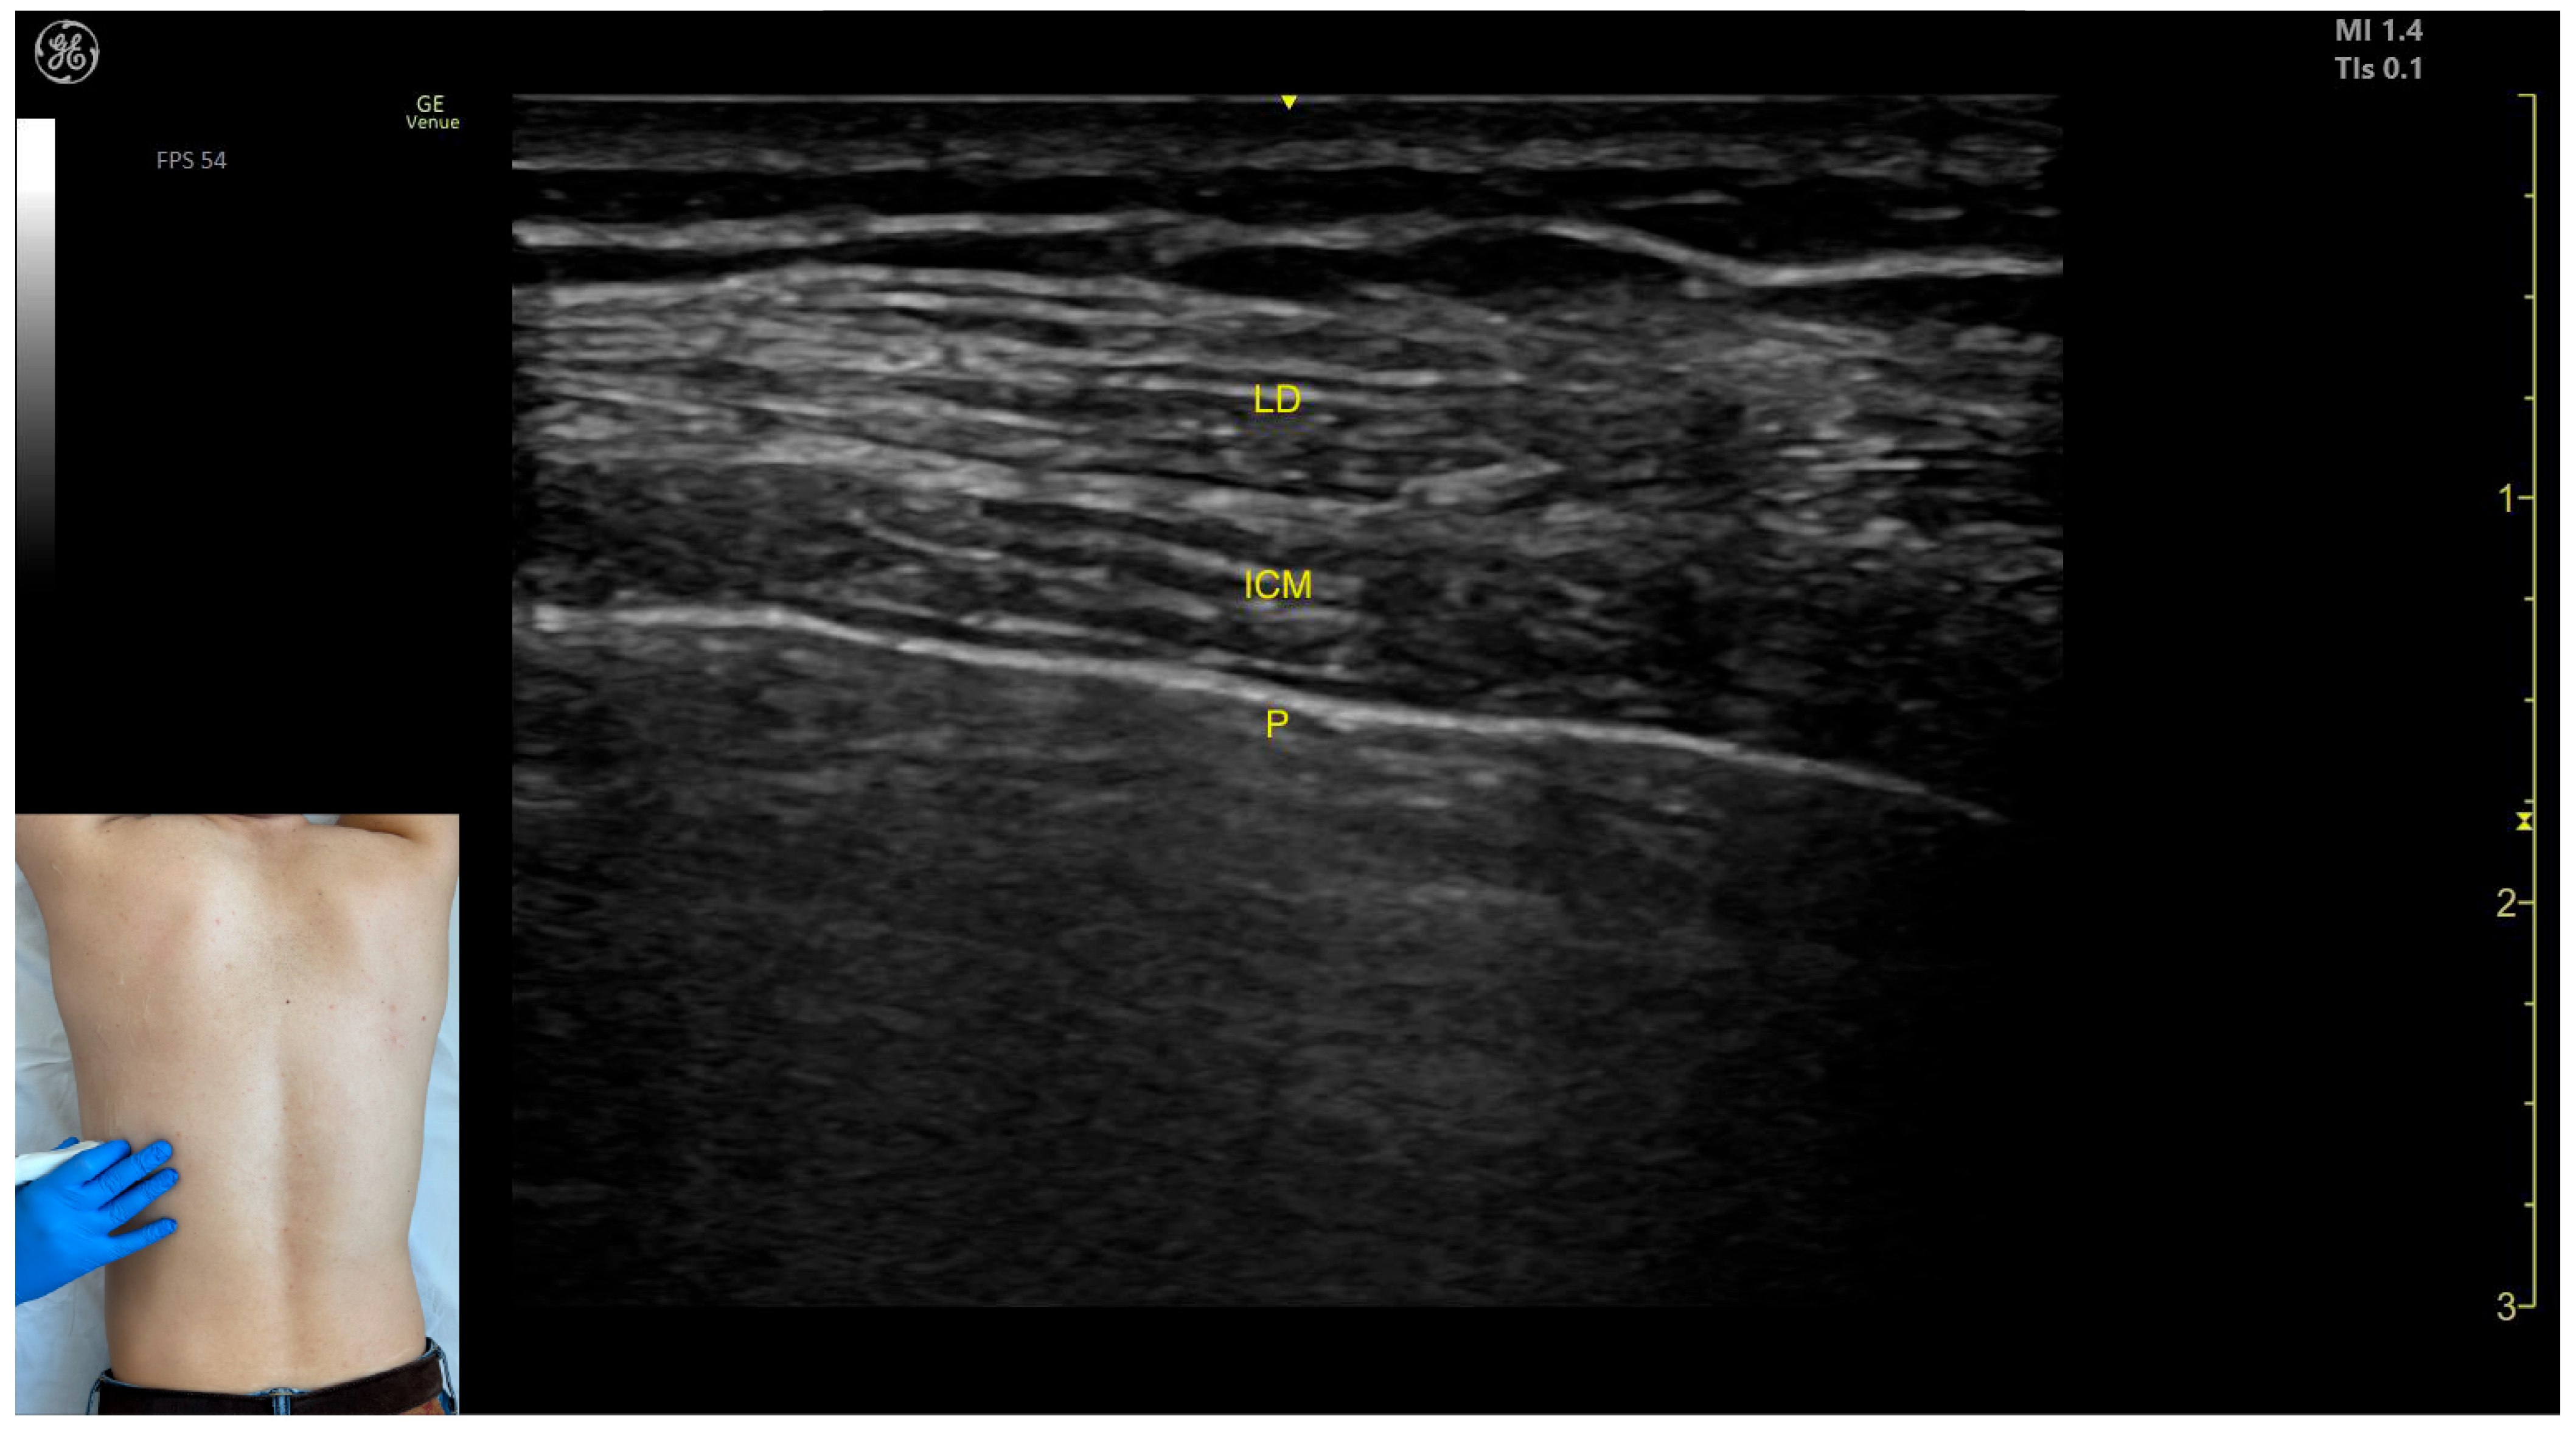

- Muscle position: The LD is the most superficial muscle mass on the posterior surface of the trunk at this level.

- Muscle morphology: It has a more pronounced fascia that separates it from the subcutaneous plane than the fascia that separates it from the intercostal muscle (ICM) muscle during BoNT-A injections.

- Dynamic evaluation: Scanning proximally (~5 cm) shows a reduction in the size of the LD and the appearance and enlargement of the serratus anterior (SA) muscle beneath it. Contraction is visible with extension, adduction, and medial rotation maneuvers of the humerus at the shoulder joint [7]. At this level the LD has a more pronounced fascia that separates it from the subcutaneous plane and the SA muscle.